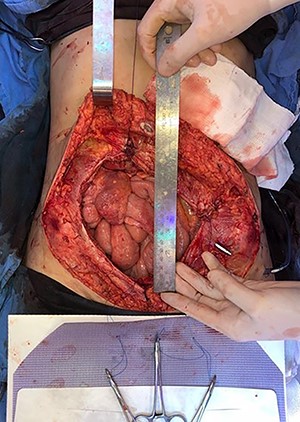

In April 2020, the surgery was performed, with pan-hysterectomy, excision of the AW and skin, pelvic peritonectomy, cecectomy (due to local involvement), partial cystectomy, Hartmann rectosigmoidectomy (Figs 4 and 5), followed by AW partial closure and an intraperitoneal onlay mesh (Open IPOM) in a bridged position with Bard Mesh/BD Sepramesh. Abdominoplasty was performed to allow skin coverage (Figs 6–10). The patient stayed in hospital for 18 days and presented urinary retention. Definitive anatomopathological was HGSC, infiltrating uterus, AW, cecum, rectosigmoid and obturator lymph node metastasis. After cytoreduction, she underwent chemotherapy (carboplatin plus docetaxel).

Mesh initially fixed on the pubic tubercle and Cooper’s ligament bilaterally.

Mesh covering the abdominal defect with presentation of transfascial fixation points, with an overlap of 8 cm.

To seek better AW functionality, fixation is crucial when the mesh is positioned like in this case, performed at symmetrical points in the remaining abdominal rectus aponeurosis, on the lateral AW, pubis and bilateral cooper ligament, in addition to a minimum 5 cm overlap to reduce the risk of hernia [10]; thus, properly distributing the tension force on the AW.